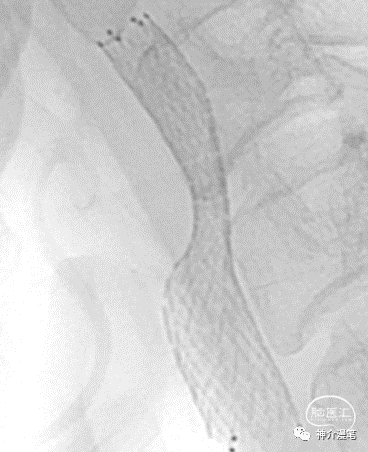

从上面这个简单的病例中可以看出,PRICISE支架对于血管局部走行的改变较小,基本顺延了原始的走行方向。这也是开环支架的一大优势。

同样,从这个病例中我们仍然能看出支架放置后血管走行的趋势没有被过度的改变。但是下面这个病例,个人觉得支架种类的选择值得商榷。

这个病例中,血管局部走行角度较大,wallsten植入后过多的改善了血管走行,让本来弯曲的血管变成一根直棍,一方面会增加局部血管的刺激造成再狭窄,另一方面血管皱褶的力度会向远端传导,造成远端血管走行变化甚至皱褶。这也是wallstent支架术后再狭窄率相对较高的重要原因,因此需要选择合适病例